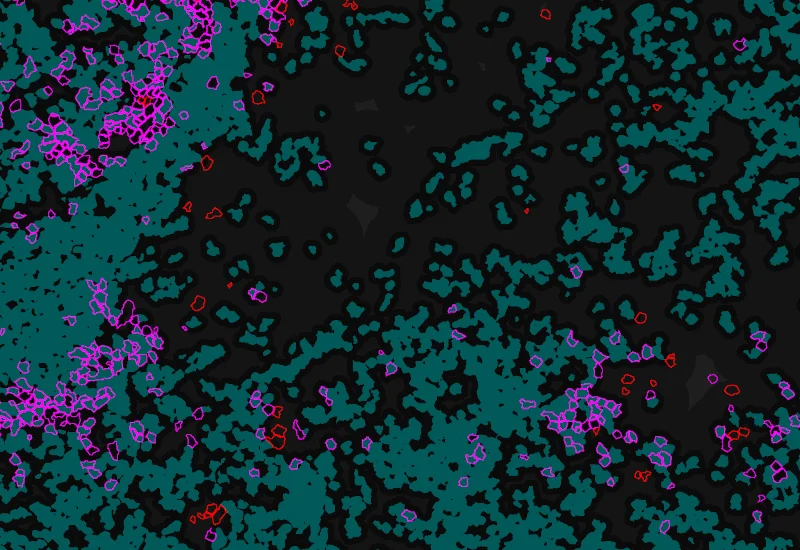

IF Cellular Contact

Determine cellular phenotypes in IF-stained samples, analyze direct cell–cell contacts, and quantify marker intensity, morphometric parameters, and number/% of contacting phenotypes.

The IF Cellular Contact App allows to determine the cellular phenotype of specific IF stained cell populations and establishes the cellular contacts to their neighboring cells (the number of markers is technically unlimited). If needed, the App provides a separation of nuclei in tissues with high cellular densities. The App outputs parameters such as staining intensity per marker and morphometric parameters for each segmented cell/cell compartment as well as number and percentage of cells of different phenotypes in direct contact.

Original Image

Nuclei detection

Phenotype 1 and Phenotype 2 detection

Phenotype 1 to 2 proximity 0-5μm

Phenotype 1 to 2 proximity 5-25μm

Phenotype 1 to 2 direct contact